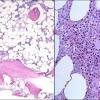

1616aplastic anemiapatients free of disease after bone marrow ... : Left:Left:aplastic anemia; Right: Normal bone marrow. ... 22, 2016, in Biology ofLeft:Left:aplastic anemia; Right: Normal bone marro